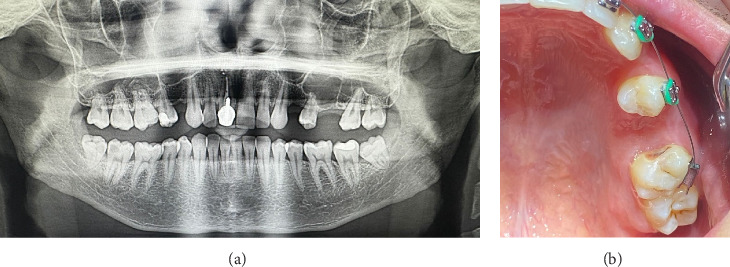

Background: Oroantral communications (OACs) are pathological openings between the oral cavity and the maxillary sinus, often resulting from dental extractions. If not treated promptly, they may lead to sinus infections and persistent oroantral fistulas (OAFs). Objective: This report aims to present a minimally invasive technique for the closure of OACs using flowable composite resin stabilized within a network of crossing sutures and to assess its clinical efficacy. Case Descriptions: Two male patients, aged 27 and 31, presented with OACs measuring 8 mm and 6 mm in diameter following maxillary molar extractions. Both cases were managed within 24-48 h postextraction. Intervention: Under local anesthesia, the extraction sockets were sutured using absorbable threads, creating a cross-matrix over the alveolus. Flowable composite resin was then applied into and over this suture network to form a sealing layer. The material was light-cured, and a secondary application was performed following socket curettage to promote stable blood clot formation. In this technique, the flowable composite is mechanically stabilized within the network of crossing sutures, which enhances the retention of the material, ensures effective sealing of the OAC, and supports a more predictable and secured healing process. Outcomes: In both cases, healing was uneventful, with complete closure of the OAC and no signs of sinusitis or fistula formation. Follow-up at 8 and 9 months confirmed successful mucosal healing and radiographic bone regeneration. Conclusion: The fixation of flowable composite within a suture matrix offers a novel, cost-effective, and reproducible technique for the immediate closure of small-to-moderate OACs. This approach enhances mechanical stability, improves sealing, and facilitates predictable healing while avoiding more invasive surgical interventions.